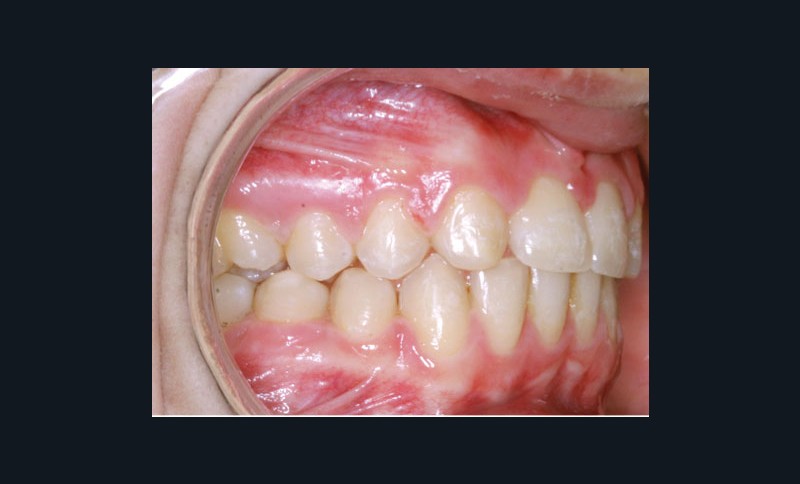

Ludivine T. âgée de 12 ans et demi présente une agénésie des deux incisives latérales maxillaires dans un contexte occlusal de classe II division 2 (fig. 1 à 3).

Les vues endo-buccales (fig. 2) montrent la classe II division 2 occlusale associée à une forte supraclusion incisive et l’évolution spontanée de 13 et 23 pratiquement en place de 12 et 22. Il persiste cependant un diastème disgracieux entre 13 et 11.